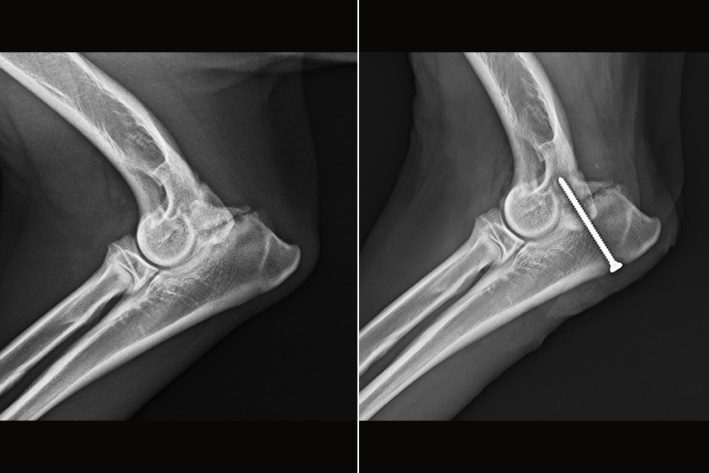

Kondylusfraktur des rechten Ellenbogens. Zum Vergleich: der linke Ellenbogen ist unauffällig.

Ellenbogen nach der Operation – Versorgung mit einer Schraube und Pin